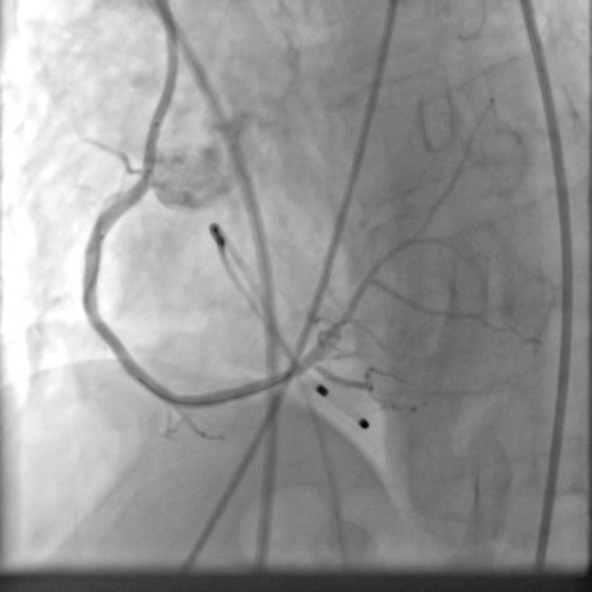

PCIof right coronary artery was initiated on IABP support with amplatz left1 guided catheter and vessel was crossed with great difficulty in repeatedattempts by fielder XT followed by GAIA 2 wire over corsair microcatheter. Microcathetercould not be crossed beyond mid segment calcified CTO, so balloon dilation with0.75 mm balloon was done after which again microcatheter could not be trackedbeyond mid part. Butwe were able to exchange wire to allstar followed by rotawire byplacing microcatheter in mid segment after balloon dilation by 0.75 mm balloon. Rotablation wasdone with 1.25 mm burr at 1,60,00 rpm repeatedly from proximal to mid distalpart. Lesionstill looked unprepared as repeated postdilation with2.25*15 mm followed by 2.5*15 mm non compliant balloon at high pressures showedunexpanded balloon. Againlesion preparation was done with 2.5*15 mm wolverine cutting balloon repeatedlyat high pressures which led to adequate luminal gain and calcium cracks as seenon IVUS run. AfterIVUS run again high pressure balloon dilation was done with wolverine 2.5*15 mmballoon followed by 2.5*12 mm non compliant balloon at 28 atm toadequately prepare the lesion before stent deployment. Stentingwas done with 2.5*32 mm DES, 2.75*32 mm DES, and 3*24 mm DES from distal toproximal in overlapping fashion. Thenfinally high pressure post dilation was done with 2.75*15 mm followed by 3*15mm non compliant balloon and adequate stent expansion was achieved with TIMI 3 flow.

Case Summary